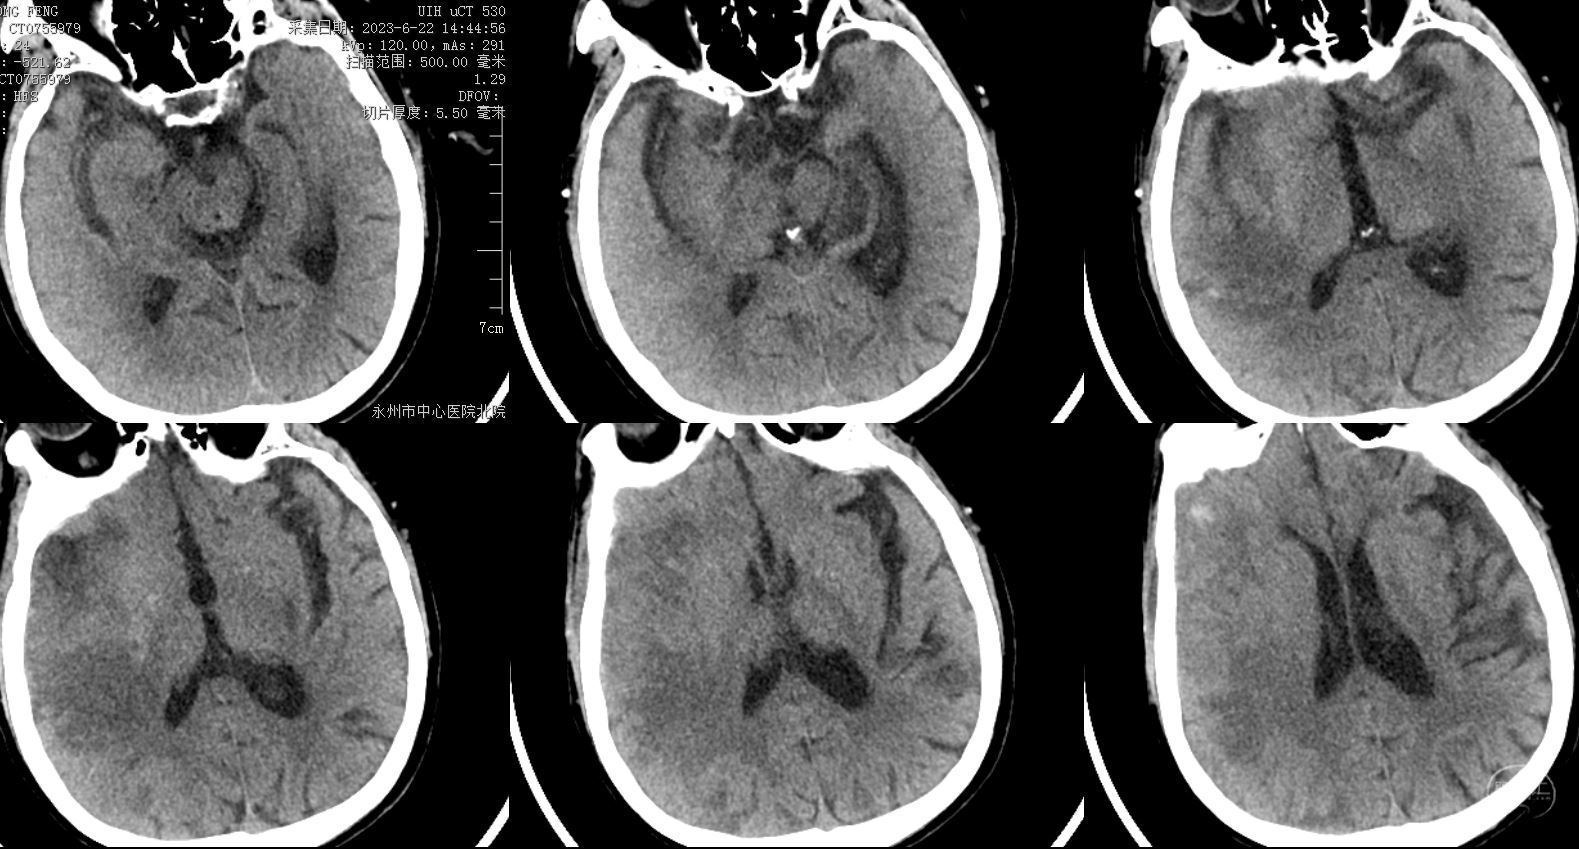

术后24小时CT,局部肿胀明显,仍可见低密度区域,但患者肢体功能改善明显。

患者术后左侧肢体功能明显改善。

总结:该患者发病时间较短,总体血栓负荷量不大,仅在大脑中动脉处取出一块红色血栓,故C1段主要考虑重度狭窄急性闭塞,置入支架就非常有必要。该患者还需要密切观察脑肿胀情况,以及其他部位病变的随访。